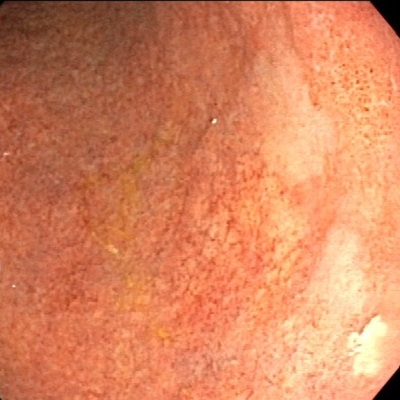

| ˆف’×ل‡(ƒsƒچƒٹ‹غٹ´گُ‚ة‚و‚é‚à‚ج) | |

| ˆف’×ل‡پAڈ\“ٌژw’°’×ل‡‚جŒ´ˆِ‚ج‘½‚‚ح ƒwƒٹƒRƒoƒNƒ^پ[ƒsƒچƒٹ‹غٹ´گُ‚ة‚و‚é‚à‚ج‚إ‚·پB ‚ـ‚½پAƒsƒچƒٹ‹غ‚جژ‘±ٹ´گُ‚حˆفٹà‚جŒ´ˆِ‚ة‚à‚ب‚è‚ـ‚·پB “–‰@‚إ‚حگد‹ة“I‚بڈœ‹غژ،—أ‚ً‚¨‚·‚·‚ك‚µ‚ؤ‚¢‚ـ‚·پB ƒsƒچƒٹ‹غ‚ج‰ًگà‚ح‚±‚؟‚ç •گ“c–ٍ•iچH‹ئ‡ٹ‚جHP‚ض‚جƒٹƒ“ƒN پ¦ƒsƒچƒٹ‹غ‚جژتگ^‚ح•گ“c–ٍ•iچH‹ئ‡ٹ‚©‚ç’¸‚«‚ـ‚µ‚½پB |